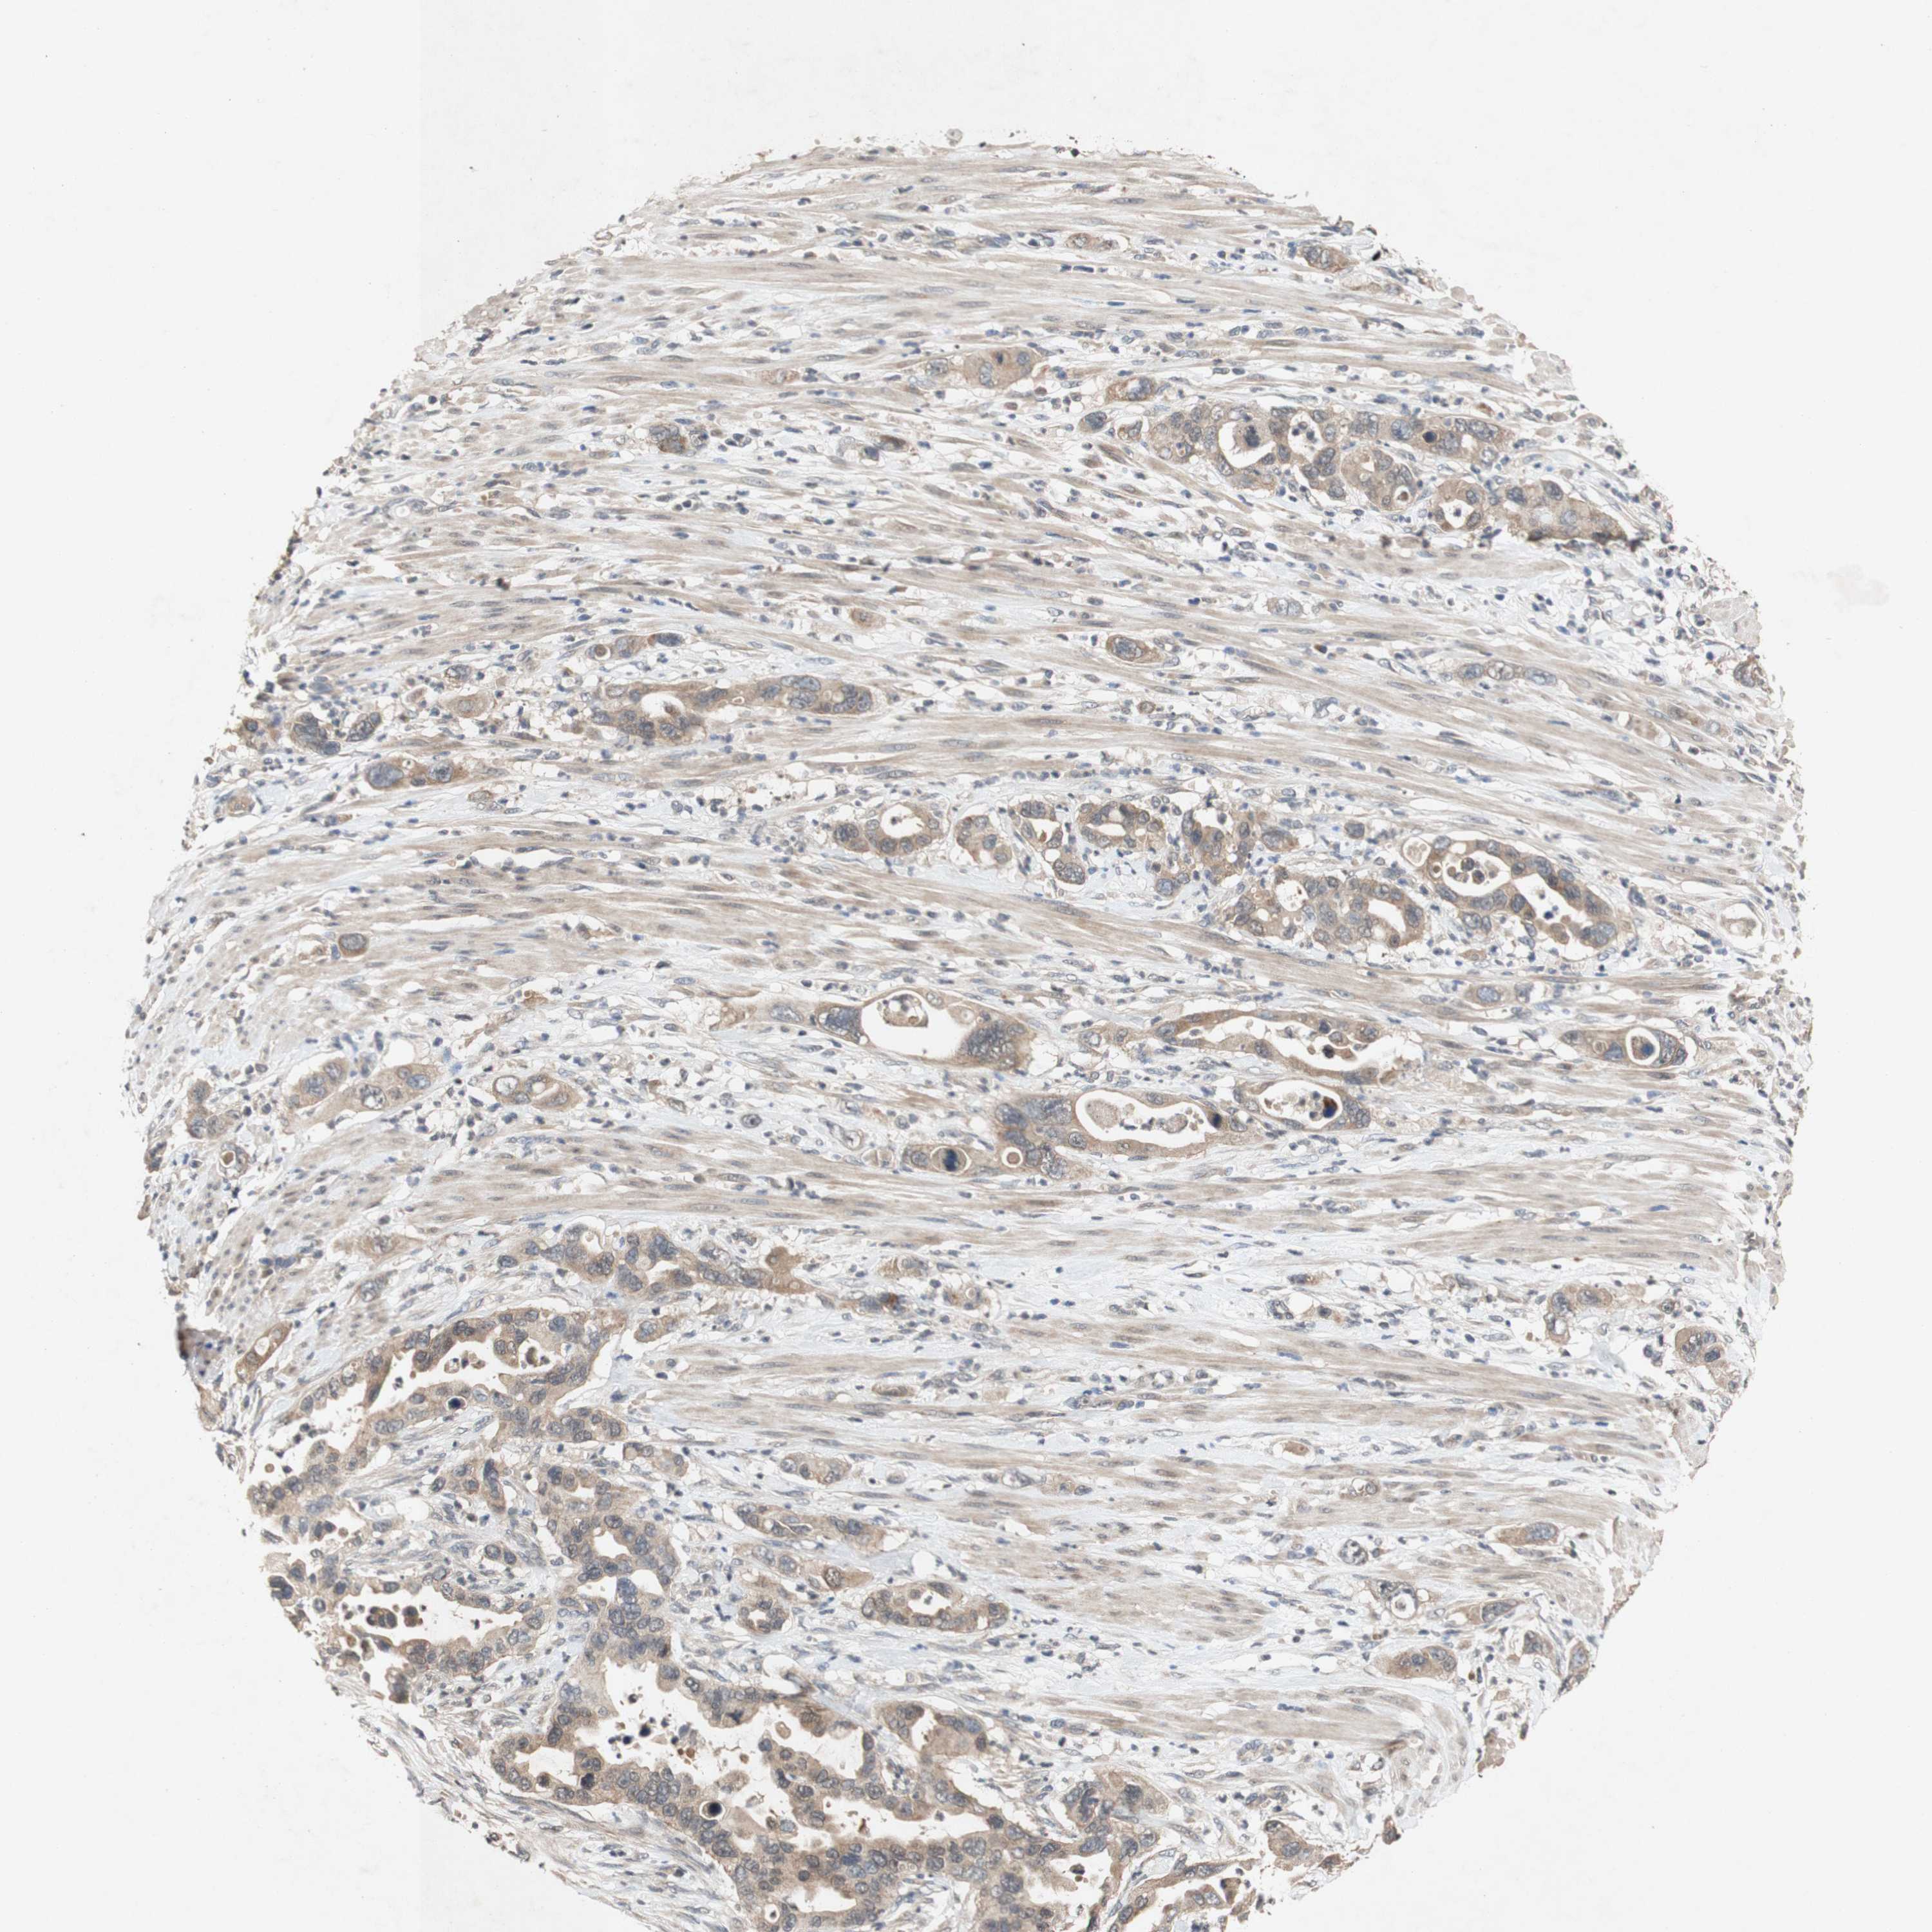

PANCREATIC CANCER - Protein expressioni

A mouse-over function shows sample information and annotation data. Click on an image to view it in a full screen mode. Samples can be filtered based on level of antibody staining by selecting one or several of the following categories: high, medium, low and not detected. The assay and annotation is described here.

Note that samples used for immunohistochemistry by the Human Protein Atlas do not correspond to samples in the TCGA dataset.

Antibody stainingi

Antibody staining in the annotated cell types in the current human tissue is reported as not detected, low, medium, or high, based on conventional immunohistochemistry profiling in selected tissues. This score is based on the combination of the staining intensity and fraction of stained cells.

Each image is clickable and will lead to virtual microscopy that enables deeper exploration of all samples and also displays staining intensity scores, fraction scores and subcellular localization as well as patient and tissue information for each sample.

Antibody CAB009326

Adenocarcinoma, NOS

Adenocarcinoma, metastatic, NOS